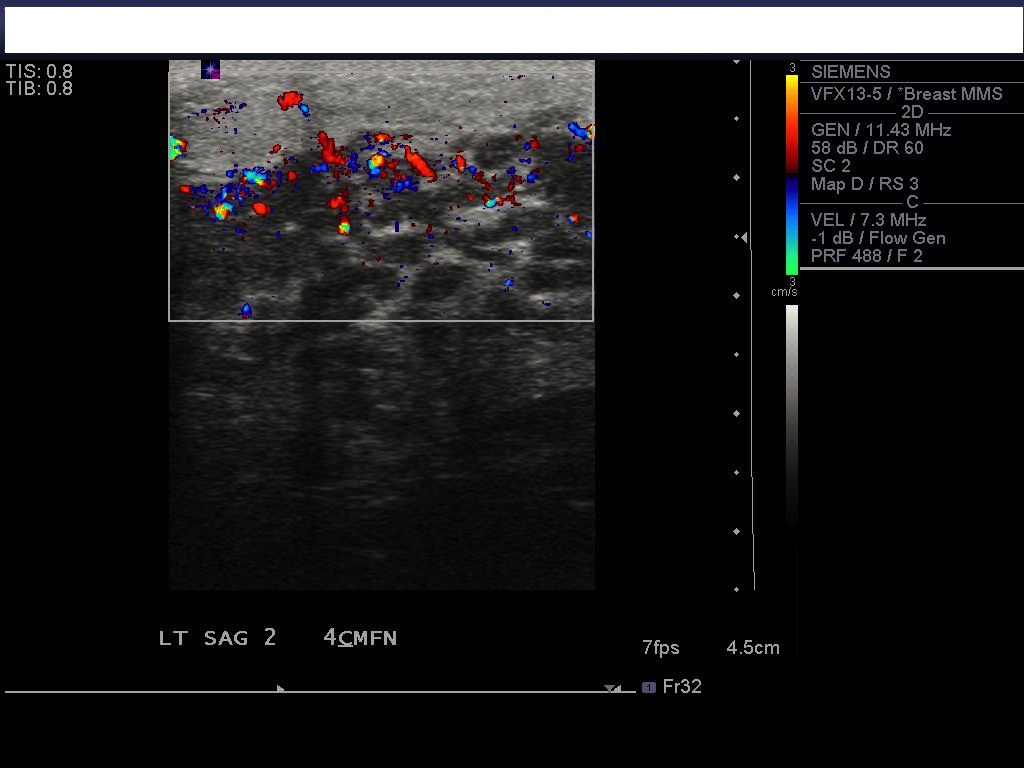

A 15 year-old girl of Bangladesh decent presented with a 2-month history of a left breast mass associated with pain and spontaneous bloody nipple discharge. She was otherwise healthy and on no regular medications. With regards to risk factors for breast cancer she reached menarche at 12 years of age, she was a nulligravida, lacked a history of thoracic radiation exposure and family history of breast or ovarian cancer.Physical examination identified breast thickening around the 12 O’clock region but no discrete masses. An ultrasound showed at the palpable area of concern, an area of dense breast tissue with dilated ducts but no discrete masses (Figure 1). She was reassured and follow up was arranged for 3 months. At follow up the palpable area in the central upper breast had increased in size and was now a defined mass roughly 4 cm in size. An MRI showed asymmetric progressive non-mass like enhancement of the left upper breast with irregular tubular enhancement and an indeterminate mass at 2 O’clock position correlating with the dilated duct seen on ultrasound (Figure 2). A mammogram, done only in medial-lateral-oblique (MLO) view to minimize radiation exposure, identified global asymmetry in the superior portion of the left breast without any suspicious calcifications or distortions (Figures 3 and 4). She subsequently underwent an ultrasound guided core biopsy with 3 core samples. The final pathology showed intraductal epithelial proliferation with increased cellularity and oedema of the surrounding stroma possibly resulting from a duct rupture. In addition, a papillary lesion with focal atypia of uncertain significance was also identified. There was no evidence of juvenile papillomatosis, in situ or invasive breast carcinoma. A second pathologist at an outside institution confirmed this report.